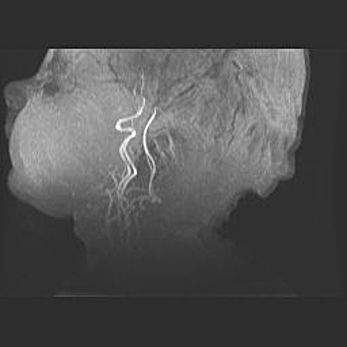

Наружная гидроцефалия с возможной атрофией височных областей.

Возраст: 28 дней

Вес: 3670 г

Пол: мужской

Окружность головы: 38 см

Срок гестации: 40 недель

Гидроцефалия головного мозга у новорожденных – это заболевание, которое характеризуется скоплением избыточного количества спинномозговой жидкости в желудочковой системе головного мозга в результате затруднения её перемещения от места выработки к месту поглощения в кровеносную систему или вследствие нарушения абсорбции. При открытой наружной форме гидроцефалии у новорожденных расширяются и переполняются субарахноидные пространства.

При нормотензивных  формах,  которые,  как  правило,  являются  следствием  перенесенных ишемических  повреждений  паренхимы  мозга,  возможно  сочетание микроцефалии  с нормотензивной гидроцефалией. В основе данных изменений лежит атрофия больших полушарий с преимущественной  локализацией  в  лобно-височных  областях.